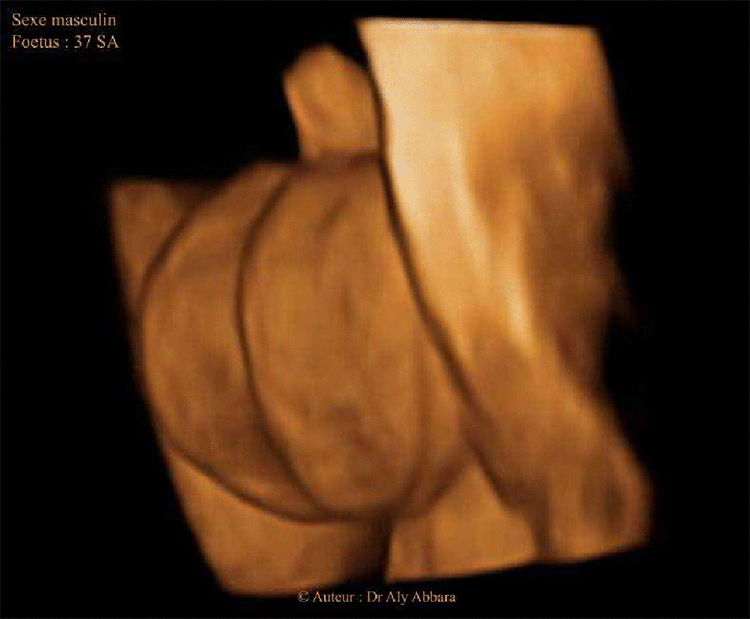

Organes génitaux externes chez un foetus du sexe masculin ; 37 SA

Images animées en 3D montrant l'aspect échographique des éléments anatomiques des organes génitaux externes chez un fœtus du sexe féminin à 33 SA et un fœtus du sexe masculin à 37 SA

Auteur : Dr Aly Abbara